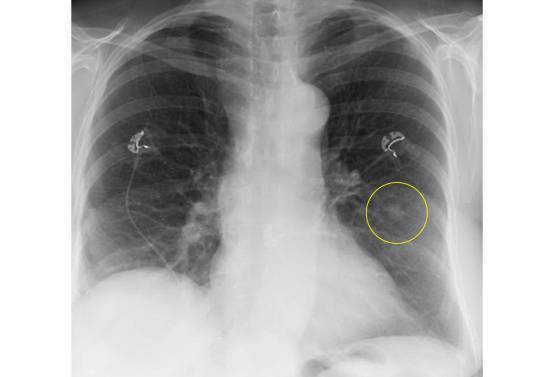

胸部x線必讀 15個容易忽視但重要的表現 醫學界急診與重症頻道 微文庫